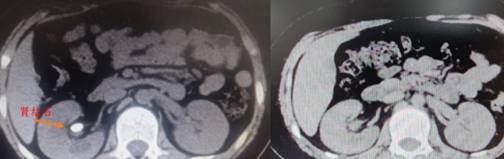

— 超微通道、完全无管化 湘雅专家为患儿清除肾脏结石 —